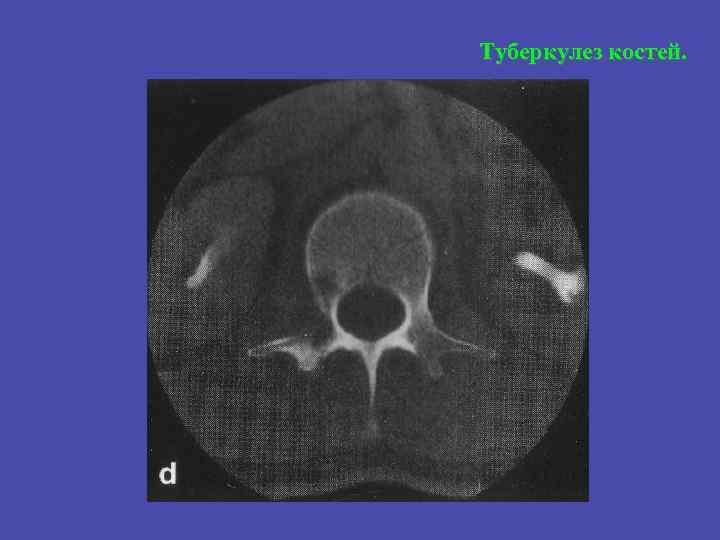

Туберкулез костей.